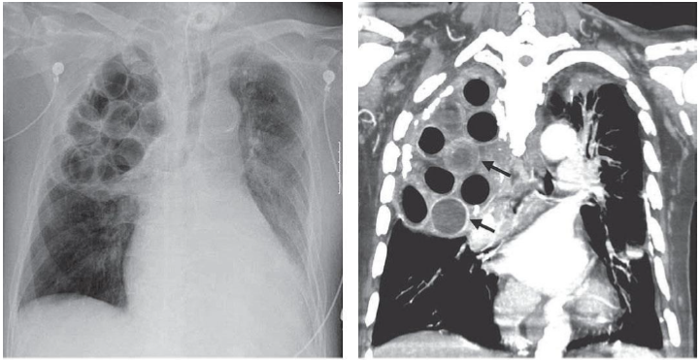

Um paciente de 70 anos foi admitido em uma Unidade de Pronto Atendimento (UPA), vítima de queda da própria altura com trauma torácico direito. Apresentava-se lúcido, eupneico e hemodinamicamente estável. Relatou história de internação e cirurgia aos 20 anos, por tuberculose pulmonar. Foi solicitada uma avaliação por imagem, obtendo-se as representações a seguir:

Fonte: Locicero e col. (2019).

Após avaliar as imagens, a equipe médica constatou que o paciente foi submetido, à época, ao procedimento cirúrgico de: